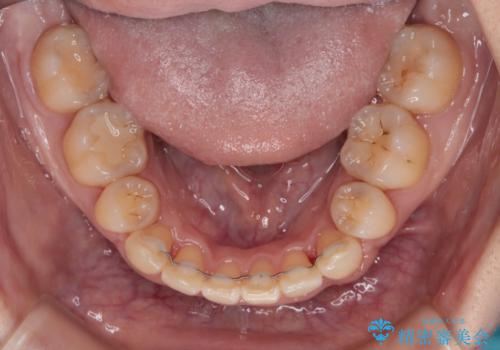

- 海外で抜歯矯正を開始し、治療途中で帰国したため、転院先を探しているとのことで来院された患者様です。

ワイヤーは抜けてしまい、後戻りが始まっている状態でしたが、既存の装置を継続利用して受け入れてくれる医院が見つからないとのことでした。

当院では、張り替える必要のある部位は張り替えることで継続することとし、抜歯スペースを閉じていくように治療を行うこととしました。